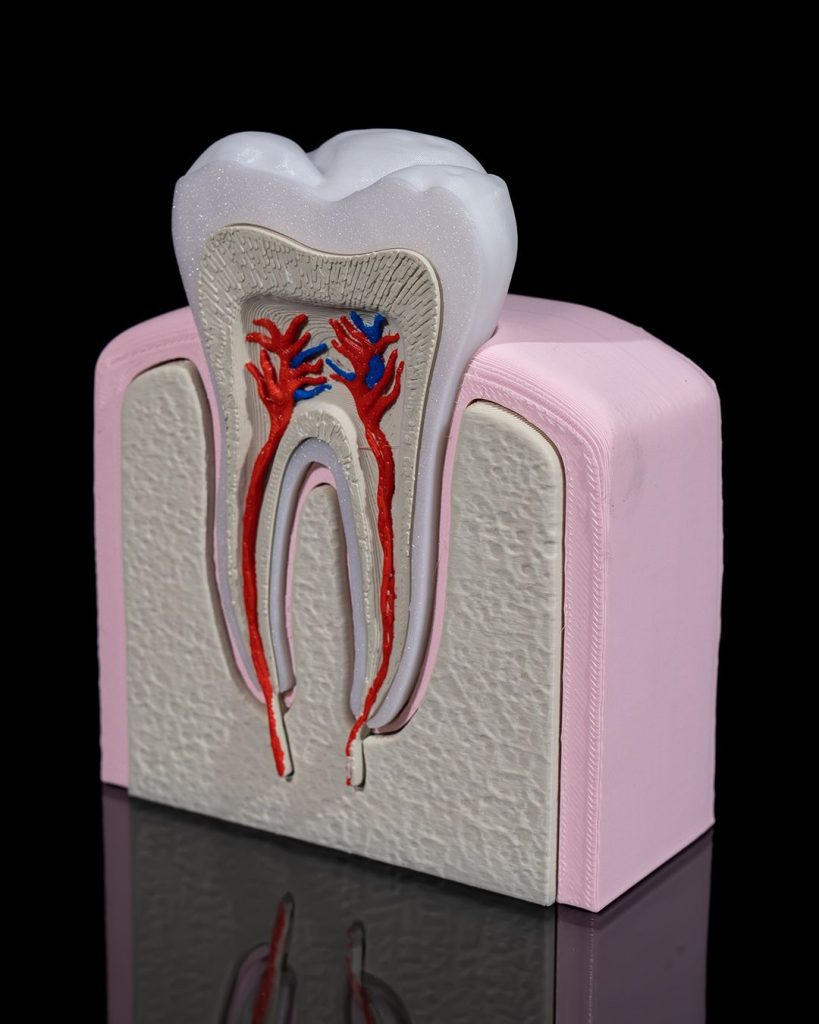

Human Tooth Anatomical Model

Example Short Description.

- Articulated and flexible for fun and display

- Intricately detailed to use

- Perfect as decor, a desk companion, or a thoughtful gift